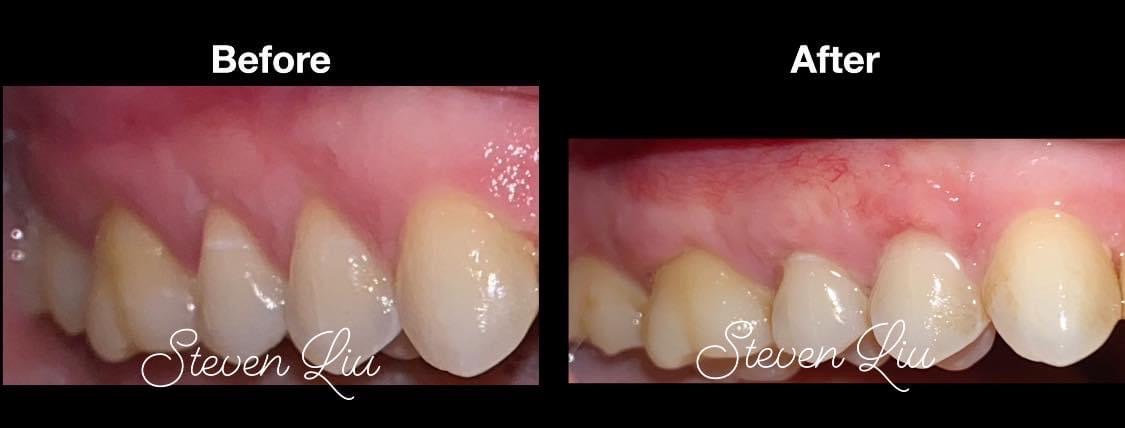

Soft Tissue Graft

Gum recession—when the gum tissue pulls back from the teeth—can cause sensitivity, aesthetic concerns, and put your teeth at risk. Dr. Liu offers several gum grafting solutions, including the innovative Pinhole Surgical Technique.

The Pinhole Gum Rejuvenation technique is a minimally invasive alternative to traditional grafting—no incisions, no sutures, and minimal downtime.

• Natural-looking results

Gum Grafting Procedure